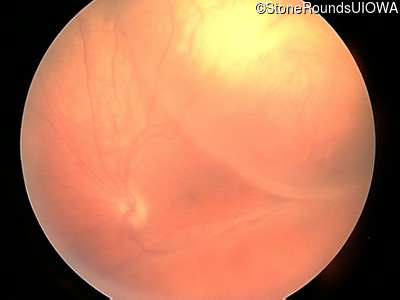

Visit at age: 14 years

Fundus Photography - Right - 20/500

Exemplar